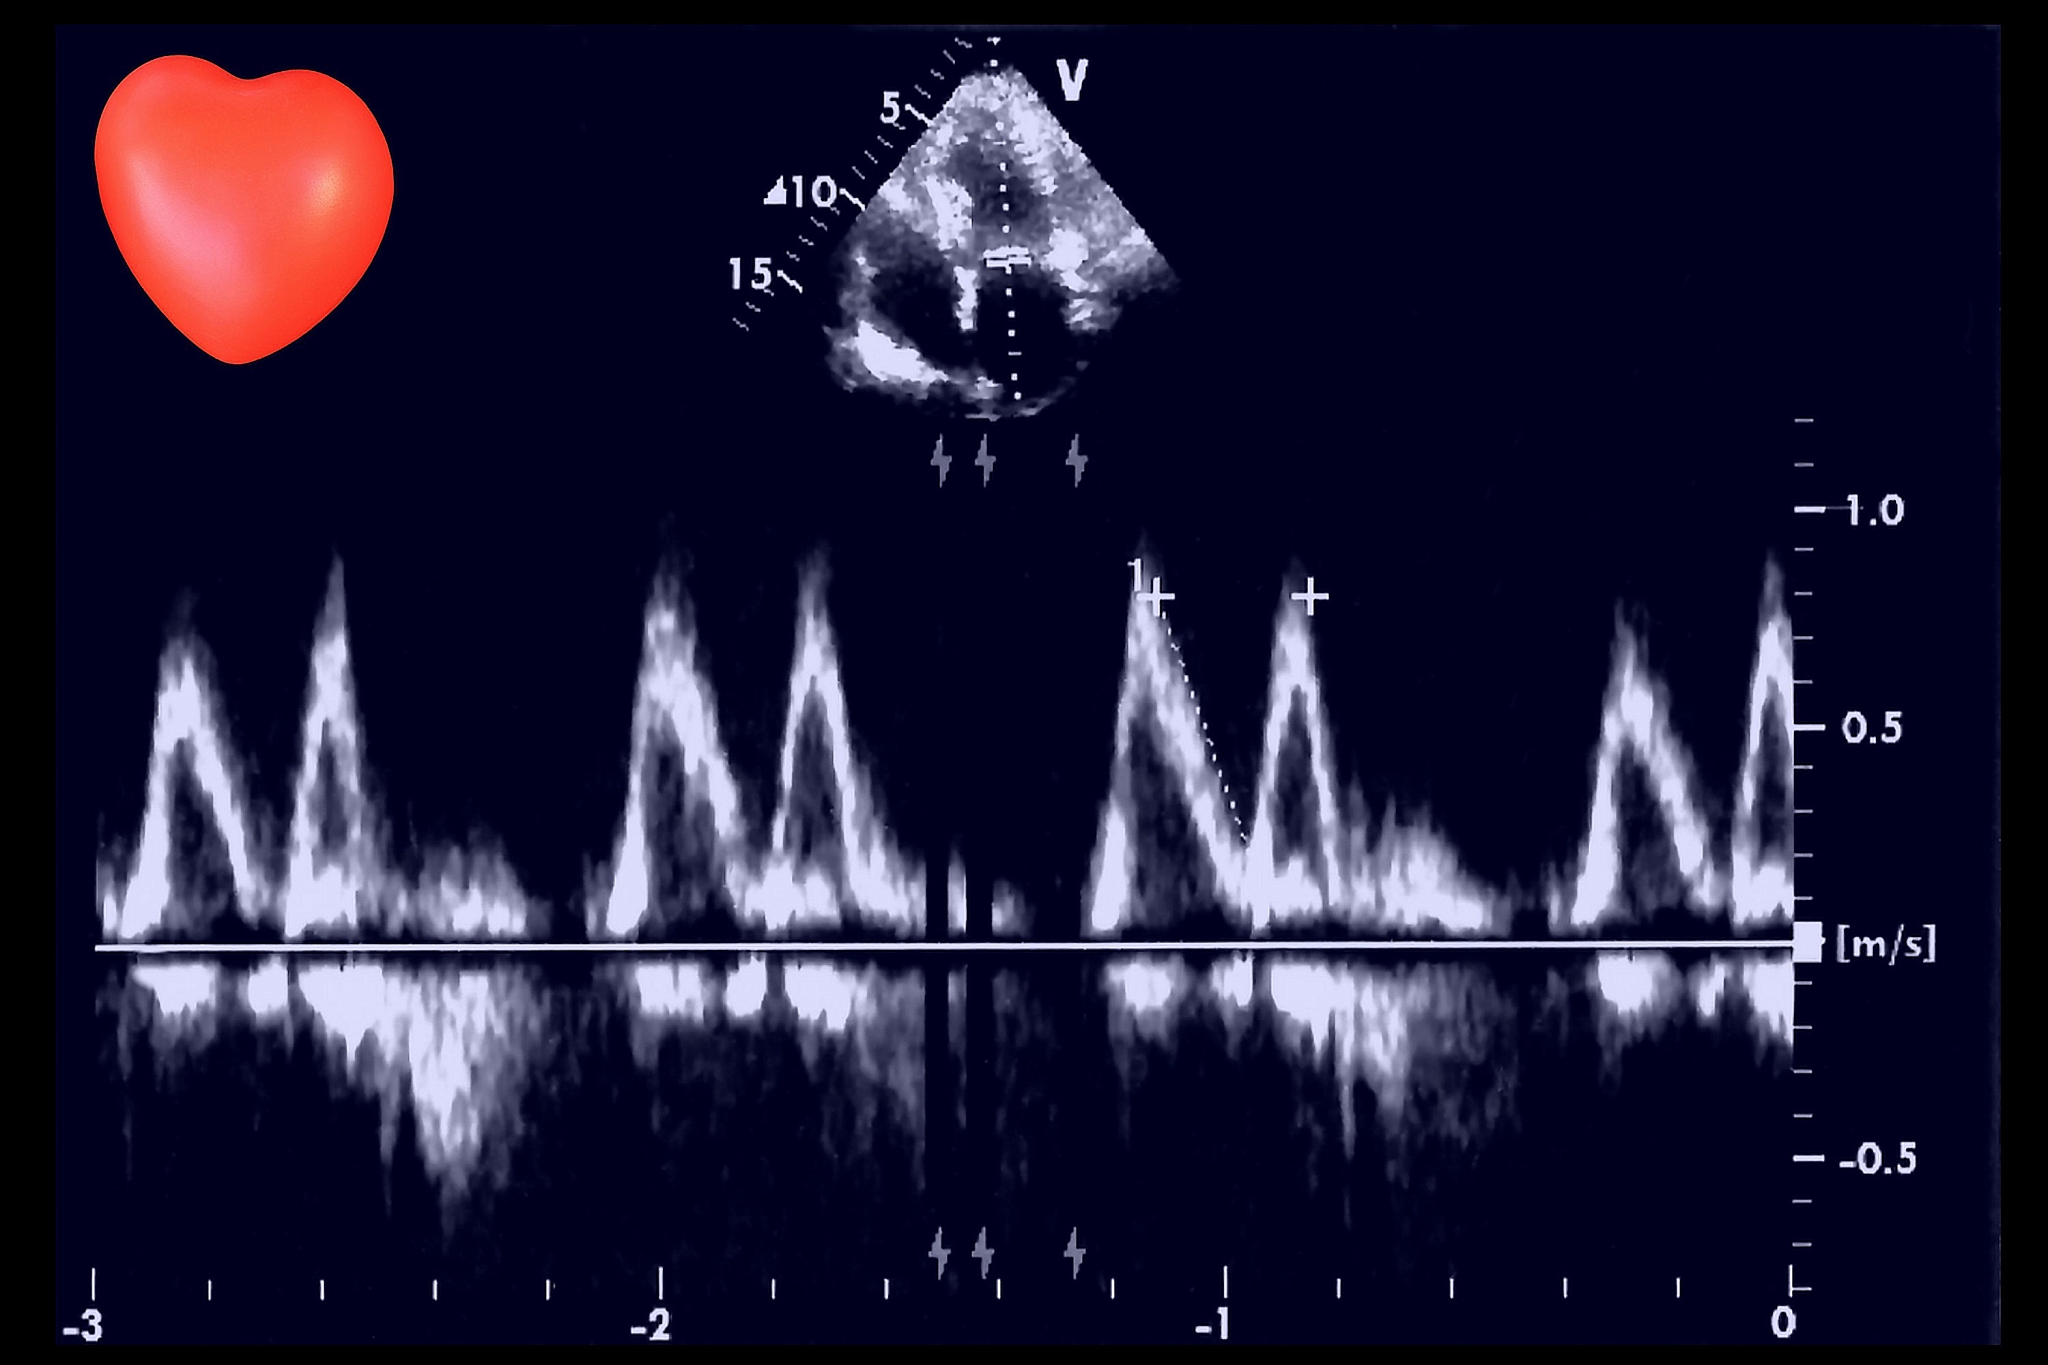

二尖瓣口血流A峰和E峰分别指二尖瓣关闭时的左心房充盈和左心室舒张时的血液回流。A峰代表左心房的收缩期,E峰代表左心室的舒张期。在心脏超声检查中,通过测量A峰和E峰的速度、比值和时差等参数,可以评估二尖瓣功能和左心室充盈状态,对心脏病的诊断和治疗有重要意义。